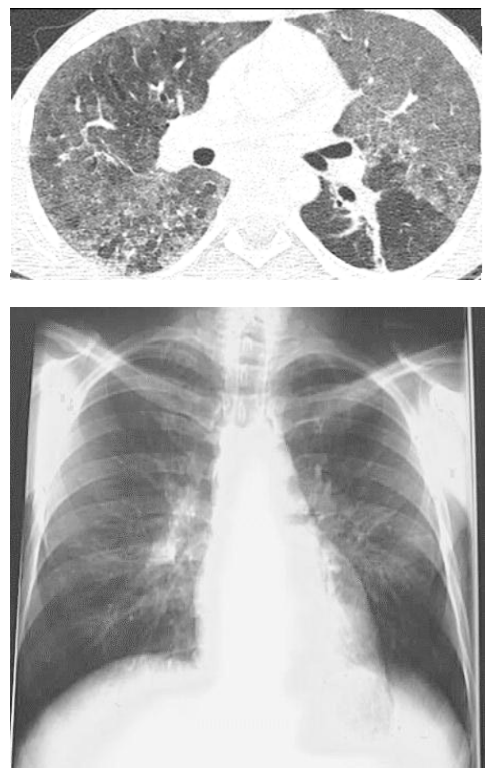

Um homem de 29 anos de idade, a princípio sem antecedentes, procurou o serviço de pneumologia com relato de dispneia progressiva, tosse seca, sensação de febre ao final da tarde e dor para deglutir. Relatou ter feito sexo desprotegido mais de uma vez no passado. Ao exame físico: lúcido e orientado em tempo e espaço; afebril; acianótico; anictérico; hidratado; taquipneico; FR de 30 irpm; FC de 60 bpm; PA de 112 × 80 mmHg; sat. de O₂ de 92% em ar ambiente; e oroscopia com placas esbranquiçadas e base eritematosa em cavidade oral. Exames complementares: Hb 13 g/dL; 15.900 leucócitos, com 7% de linfócitos e 70% de neutrófilos, com desvio à esquerda; 264.000 plaquetas; escarro com BAAR negativo; e DHL 900 U/L. Gasometria: pH 7,44; PO2 62 mmHg; PCO2 22 mmHg; e BIC 26.